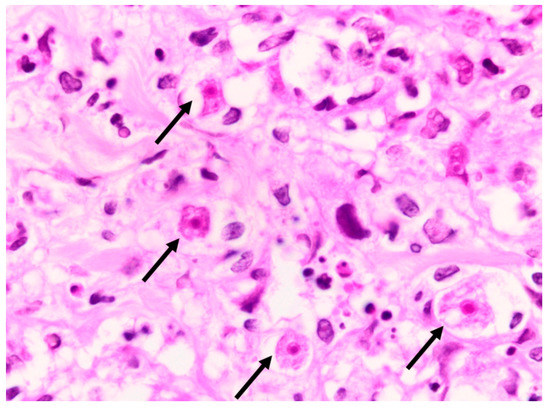

A deep skin punch biopsy was obtained from one of the lesions on the forearm, and submitted in 10% buffered formalin. The haematoxylin and eosin-stained sections revealed a polymorphous nodular deep dermal and subcutaneous inflammatory cell infiltrate comprising neutrophils, histiocytes, lymphocytes and eosinophils in response to conspicuous numbers of free-living amoebic organisms (Figure 5). Each round trophozoite was seen to possess a characteristic targetoid eosinophilic nucleus (Figure 6). Only rare, encysted forms were noted in the inflamed areas. Occasional subcutaneous vessels showed vasculitis. Erythrophagocytosis was conspicuously absent. There was no preponderance of histiocytic giant cells. The periodic acid-Schiff (PAS) stain was positive in some of the organisms, but the Grocott methenamine silver, TriPAS and Ziehl-Neelsen stains were negative. A diagnosis of cutaneous acanthamoebiasis was rendered, and the infectious diseases service was consulted. Further skin biopsies were sent to the national reference parasitology laboratory at the National Institute for Communicable Diseases (NICD). Cultures and PCR testing of the isolate performed at the NICD according to published methods [8,9] confirmed the presence of an Acanthamoeba species, with further 18s rRNA gene-sequencing identifying the isolate as a T4 strain, Acanthamoeba polyphaga (>99% identity with GenBank sequence accession no. MN153018.1).

Figure 5. Photomicrograph of skin punch biopsy showing numerous amoebic organisms (arrows) and a polymorphous background inflammatory infiltrate (haematoxylin and eosin, ×400).

Figure 6. Acanthamoeba organisms (arrows), as seen under oil immersion. Note the characteristic targetoid appearance of the nuclei (haematoxylin and eosin, ×1000).